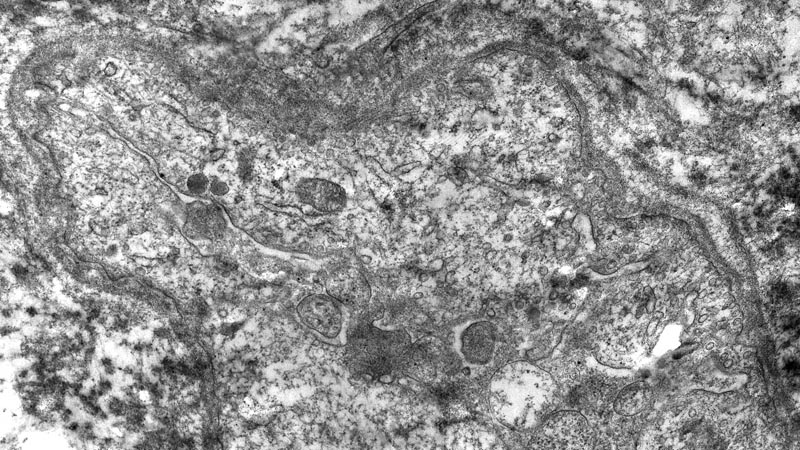

Капилляр из миокарда больного ишемической болезнью сердца.